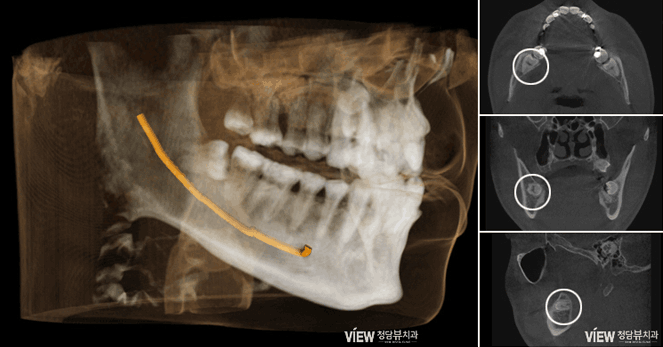

3D CT 등 첨단 디지털 장비를 통한 정밀 진단

정밀검사를 토대로 사랑니 발치 계획 수립

수평으로 누운 매복사랑니는 바로 절단한 후 남아있는

치아를 파절시켜 제거